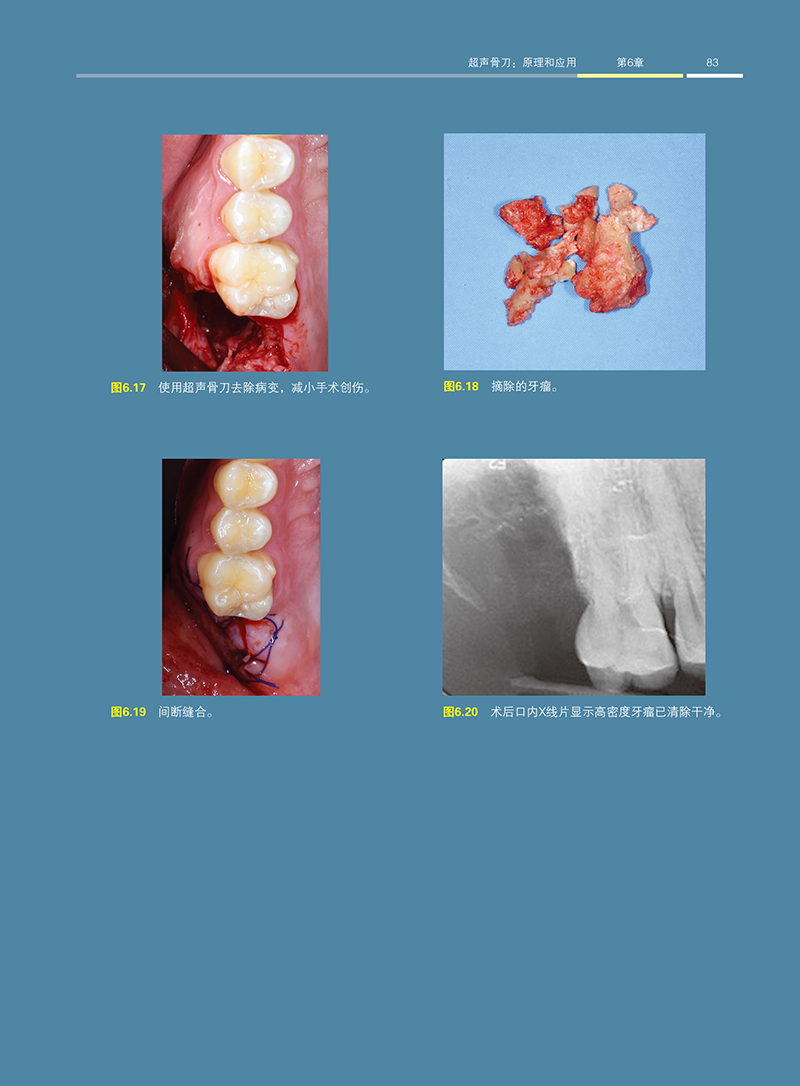

超音波骨刀在阻生牙拔除的應用:出版時間:2023年1月

本書總結了一套幾乎可以應對所有拔牙病例的操作技巧。另外,即使是在阻生牙拔除上沒有過多臨牀經驗和學習經歷的牙醫,通過本書學習超聲骨刀的應用,也能應對臨牀各種的複雜情況,緩解患者的焦慮情緒。

本書全方位介紹了超聲骨刀的臨牀應用價值,系統講解超聲骨刀在不同阻生牙拔除中的使用,以及牙槽外科相關基礎知識,內容涵蓋解剖、藥理、外科基本操作、相關藥物應用、併發症的防治和處理等,對於臨牀醫生系統提升專業水平具有一定的參考性。